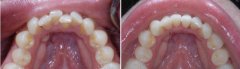

不同程度的四环素牙如何美白?

四环素牙是在牙发育矿化期,服用的四环素族药物,可被结合到牙组织内,使牙...【详细】